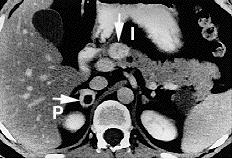

- 부신 갈색세포종: 노르에피네프린과 에피네프린이 과도하게 분비되어 혈관 저항이 증가하고 고혈압을 유발하는 질환이다.[20][21] 비선택적 α1 및 α2 차단제인 페녹시벤자민이 사용된다.[21]